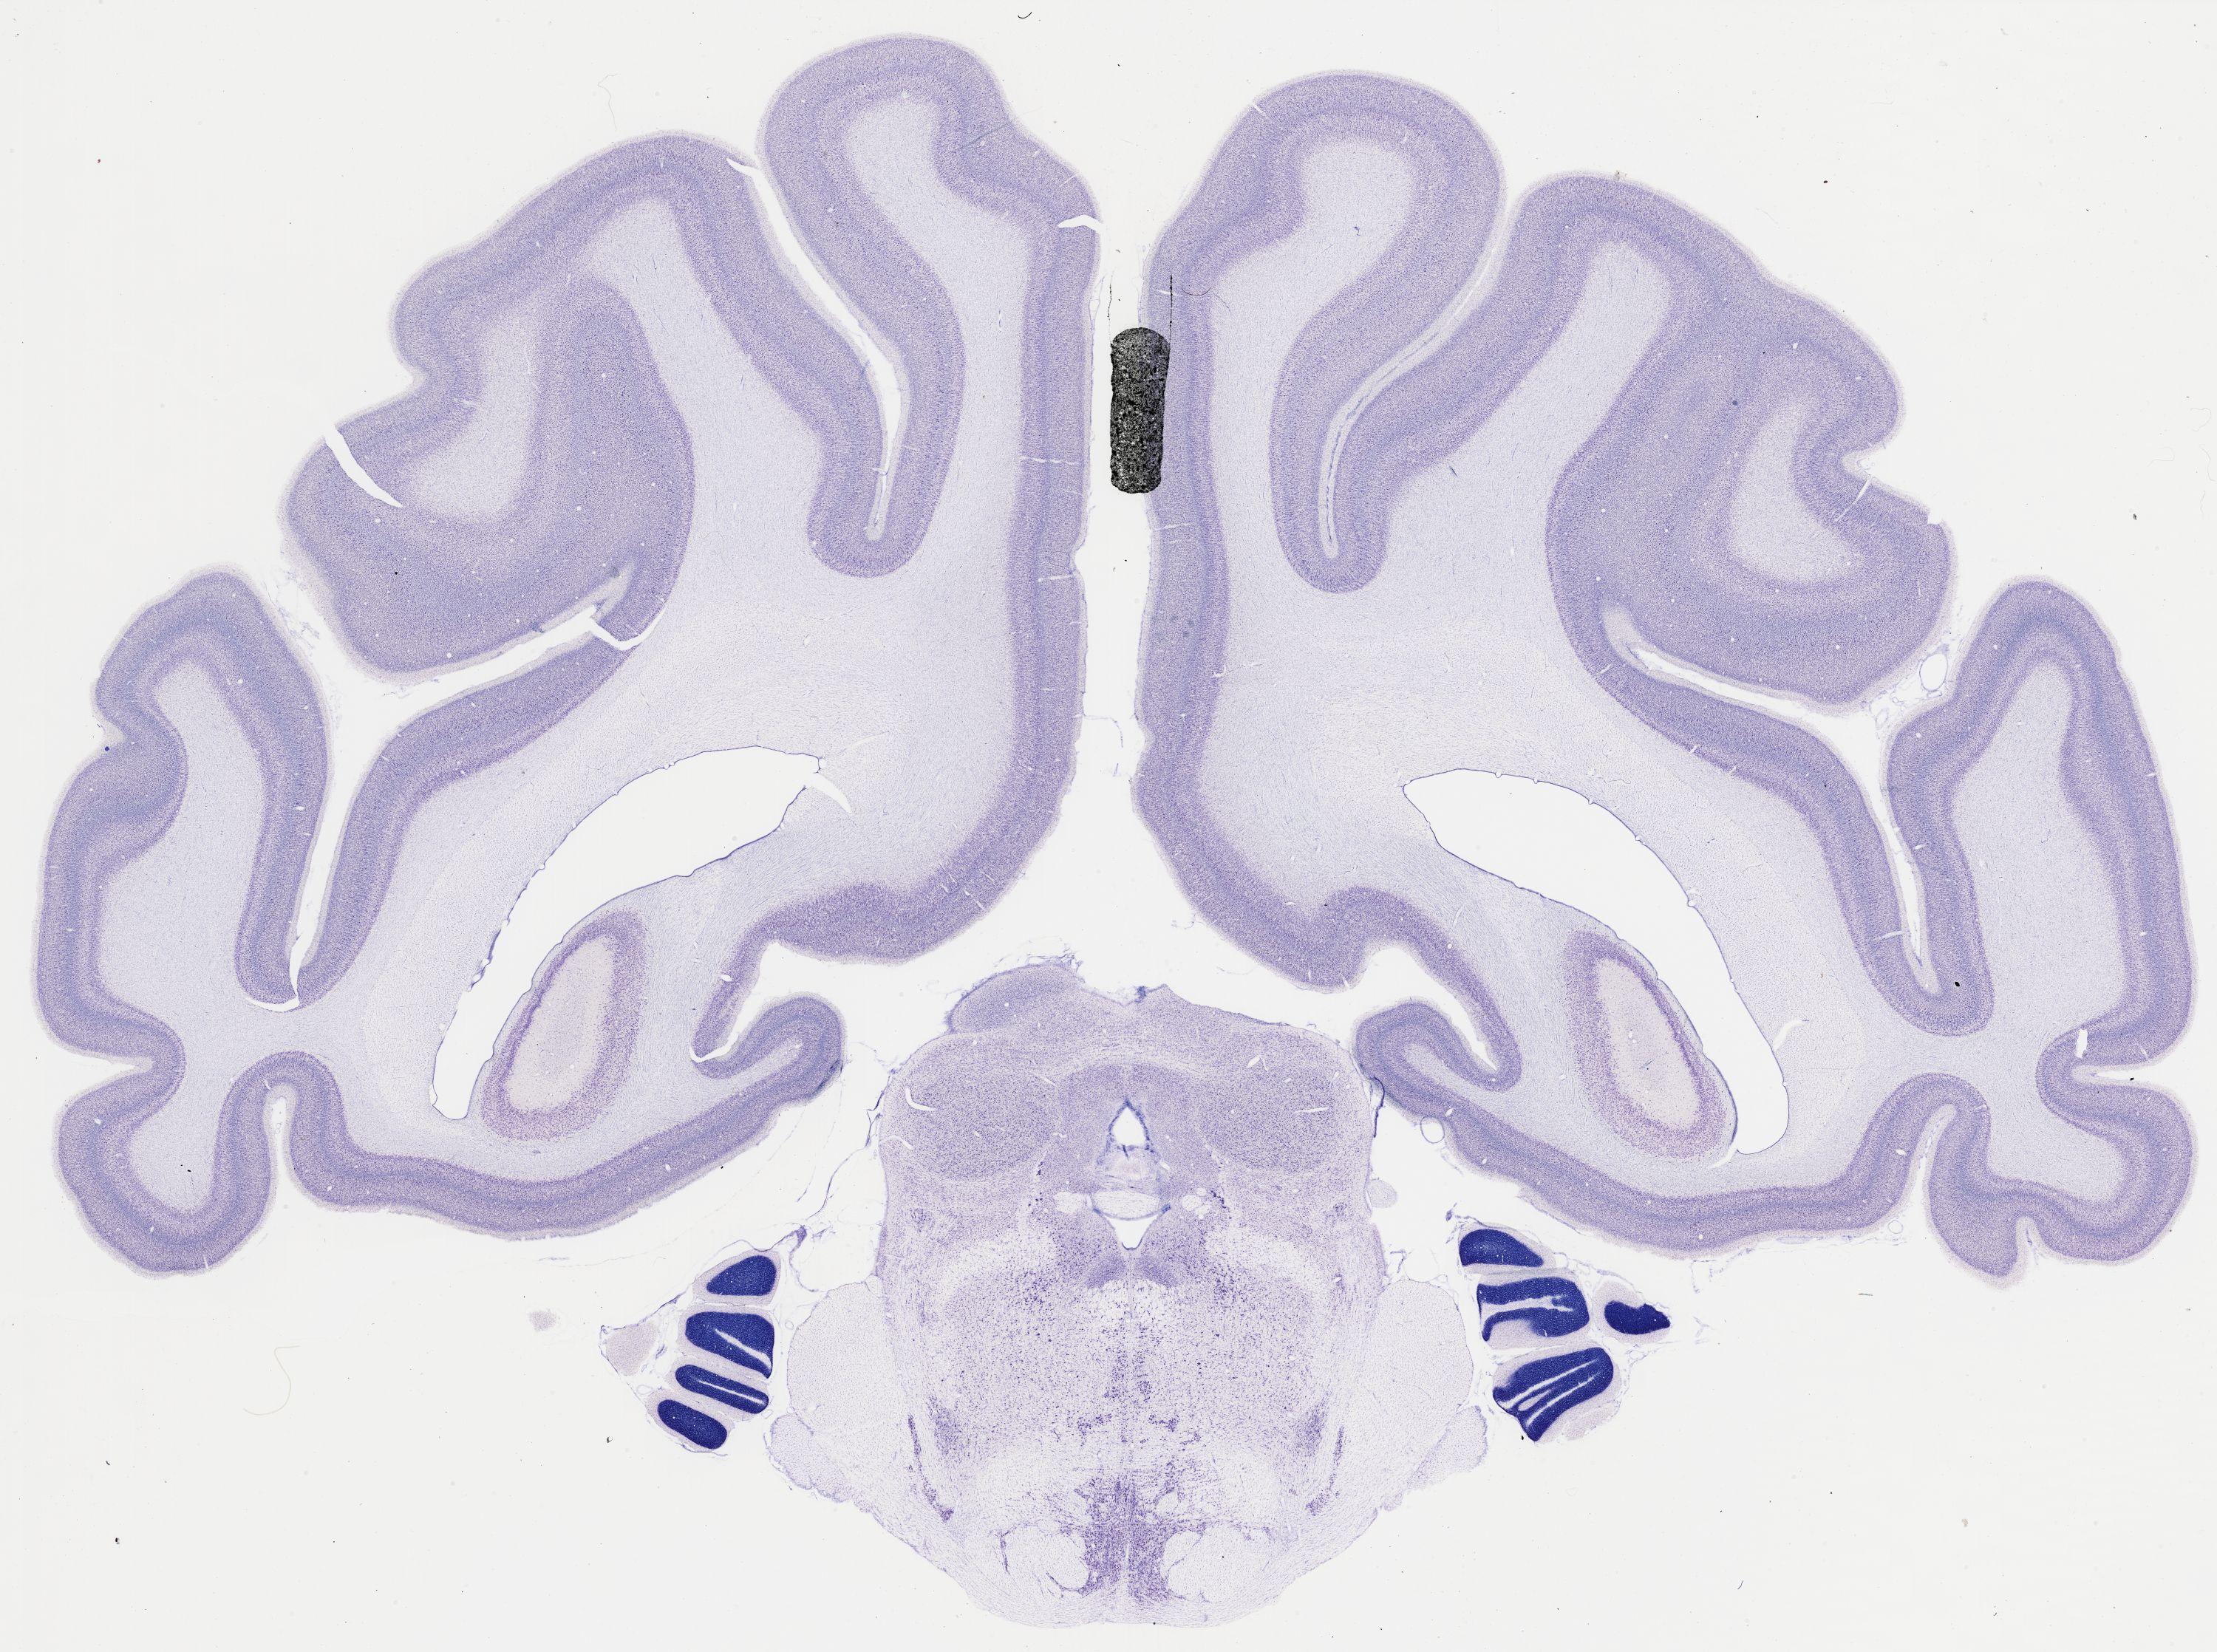

thumbnail

484